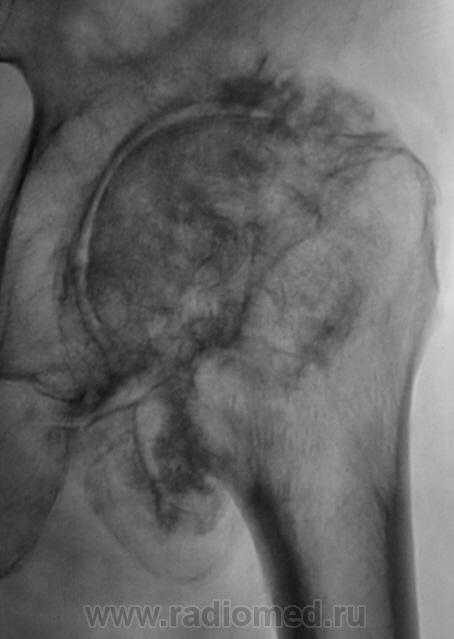

"Спинальный больной". Наблюдение Бородулина М.А. Наблюдение Бордулина М.А. Наблюдение Катенёва В.Л. Пт, 06/07/2012 - 21:41 #1 Наталия Васильевна Не на сайте Был на сайте: 5 лет 7 месяцев назад Зарегистрирован: 25.09.2011 - 09:02 Публикации: 754 А возможны ли такие изменения при сирингомиелии? Пт, 06/07/2012 - 22:22 #2 Катенёв Валенти... Не на сайте Был на сайте: 6 лет 11 месяцев назад Зарегистрирован: 22.03.2008 - 22:15 Публикации: 54876 По всей видимости - да. Пт, 06/07/2012 - 23:03 #3 И.Бондаренко Не на сайте Был на сайте: 1 день 9 часов назад Зарегистрирован: 13.09.2011 - 22:55 Публикации: 9199 Считайте ,что такие изменения сопутствуют сирингомиелии. Пт, 06/07/2012 - 23:08 #4 Катенёв Валенти... Не на сайте Был на сайте: 6 лет 11 месяцев назад Зарегистрирован: 22.03.2008 - 22:15 Публикации: 54876 И.Бондаренко wrote: Считайте ,что такие изменения сопутствуют сирингомиелии. +1 Сб, 07/07/2012 - 22:10 #5 Наталия Васильевна Не на сайте Был на сайте: 5 лет 7 месяцев назад Зарегистрирован: 25.09.2011 - 09:02 Публикации: 754 Ну, тогда, действительно-"спинальный больной".

А возможны ли такие изменения при сирингомиелии?

По всей видимости - да.

Считайте ,что такие изменения сопутствуют сирингомиелии.

Ну, тогда, действительно-"спинальный больной".